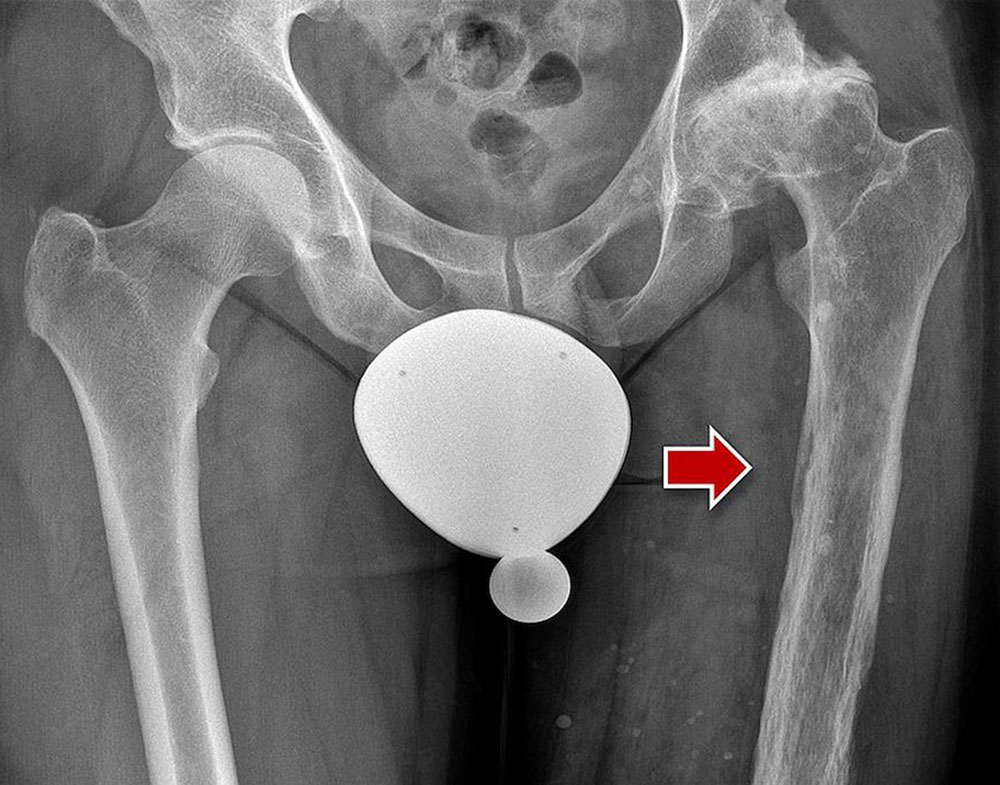

Occasionally phleboliths are visible on conventional images in patients with venous malformation.

Phleboliths are pathognomonic for the presence of a venous malformation outside the pelvis. In patients with arteriovenous malformation, the cortex of an affected bone may be thickened or lytic. Not infrequently, tubular defects are also recognizable in intraosseous AVMs.